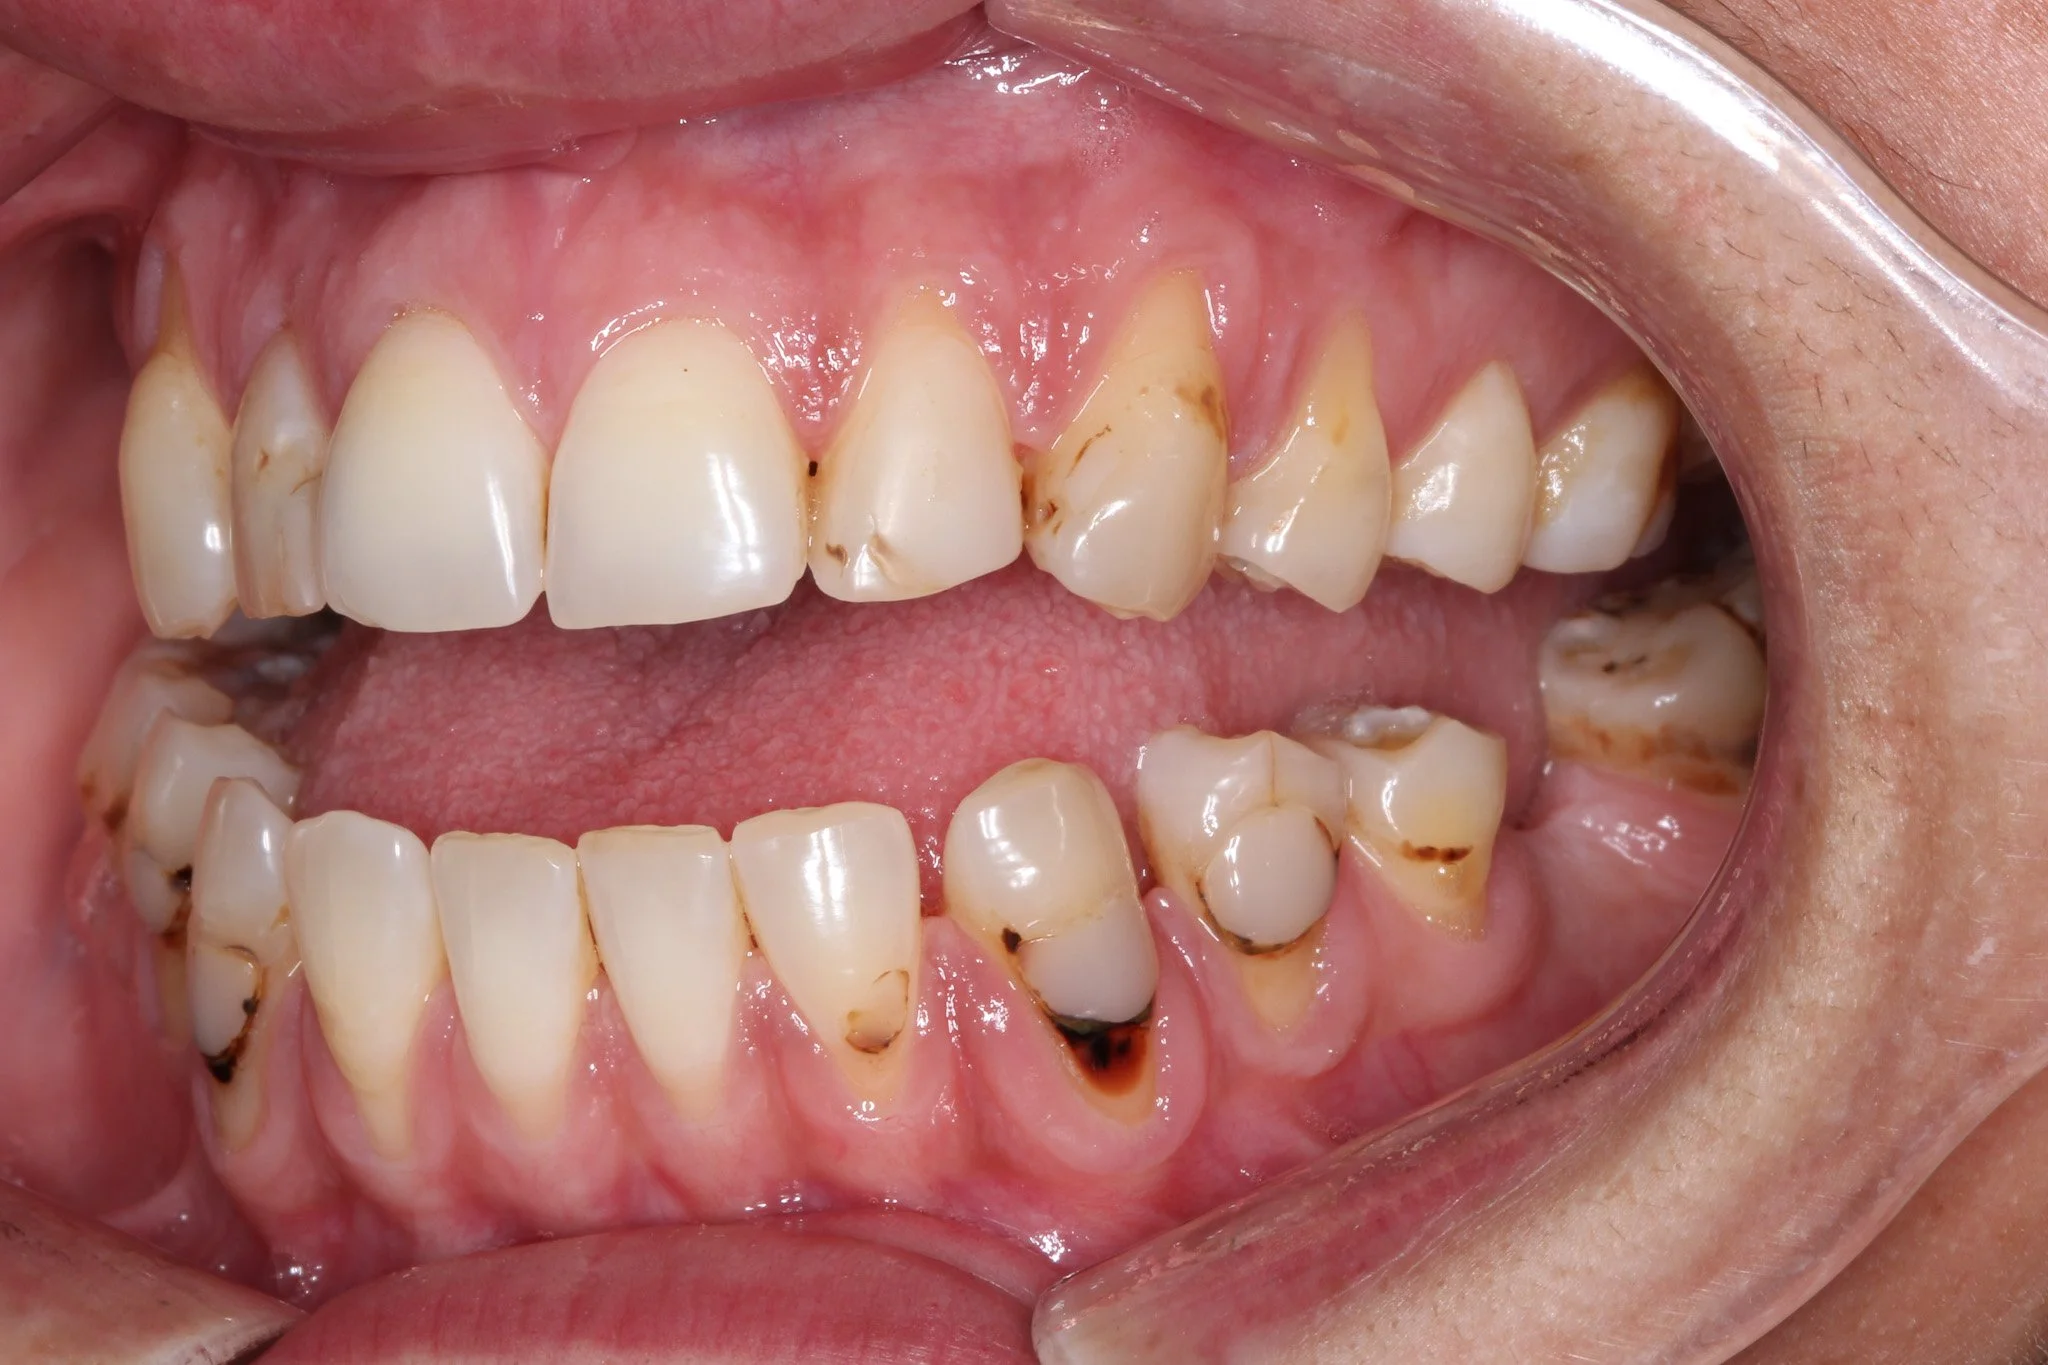

The margin of the filling here is stained and visible

Visible filling margins that have gathered a lot of staining